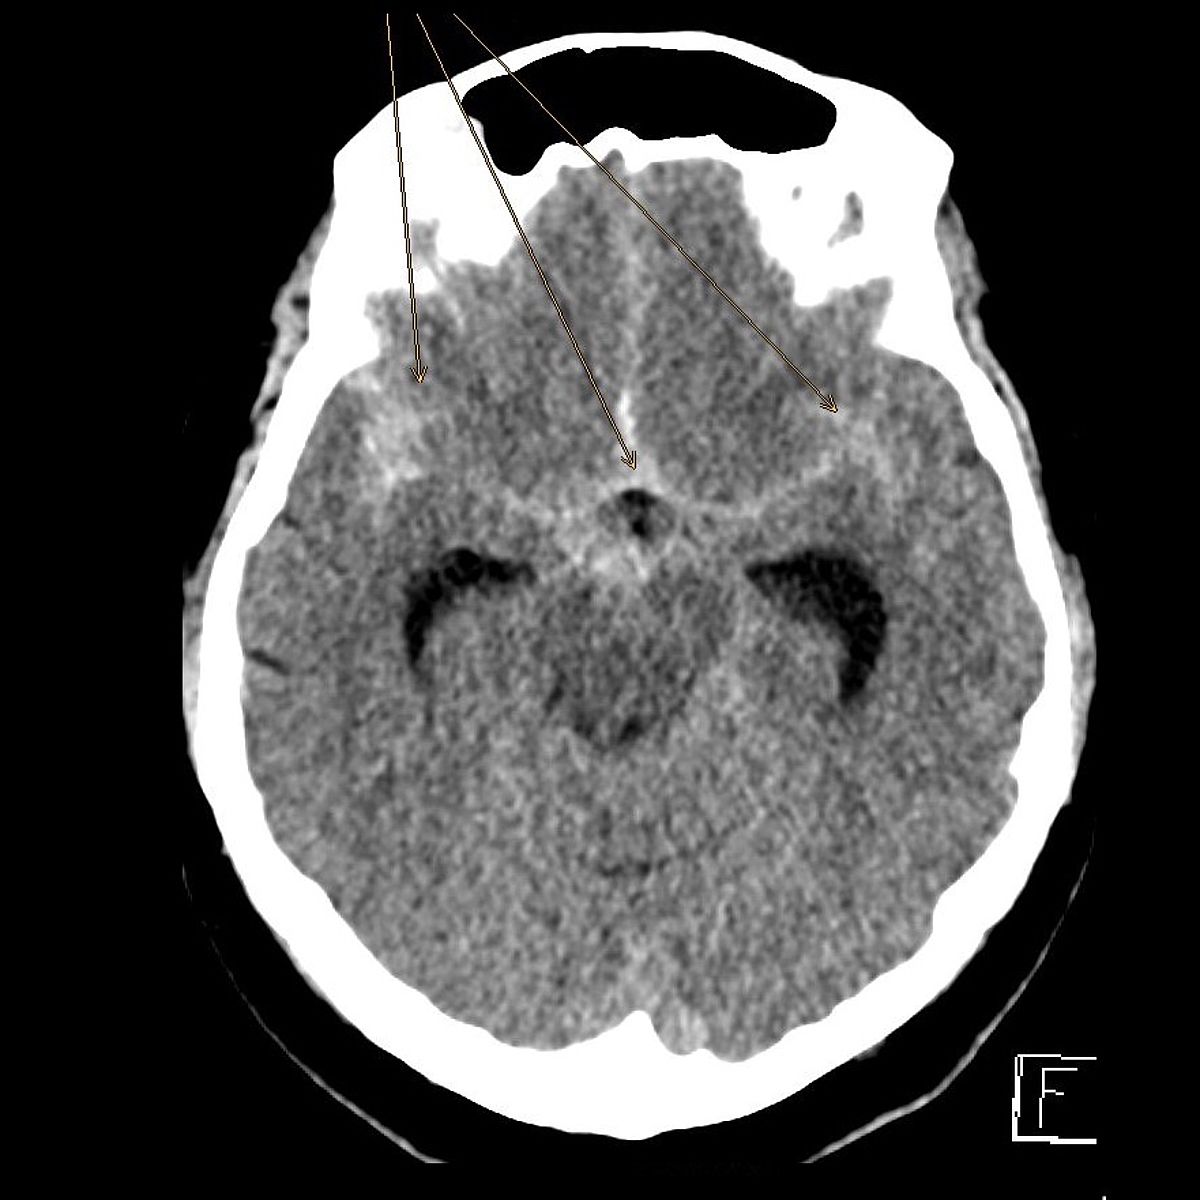

Die Hauptgefahr geht von einem Riss eines solchen Aneurysmas aus, was zu einer lebensgefährlichen Blutung in die Gehirnhäute oder das Gehirn führen kann (Subarachnoidealblutung).

In Augsburg werden im Jahr etwa 80 solcher akuter Subarachnoidealblutungen behandelt. Dabei ist neben der Behandlung der Blutungsfolgen vor allem die Ausschaltung des ursächlichen Aneurysmas dringlich, was meist interventionell durch die Neuroradiologie erfolgt.